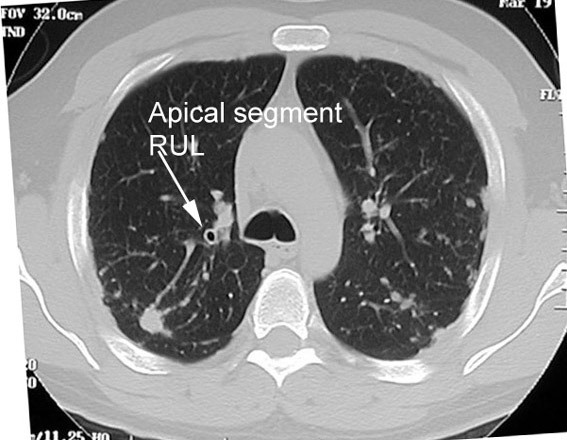

Q: Click to look at the section at the level of Carina. Identify the bronchial segment the arrow is poiniting to.

Answer

Apical segmental bronchus of RUL

Since the apical segment of RUL is vertical, section at this level gives a circular lucency.